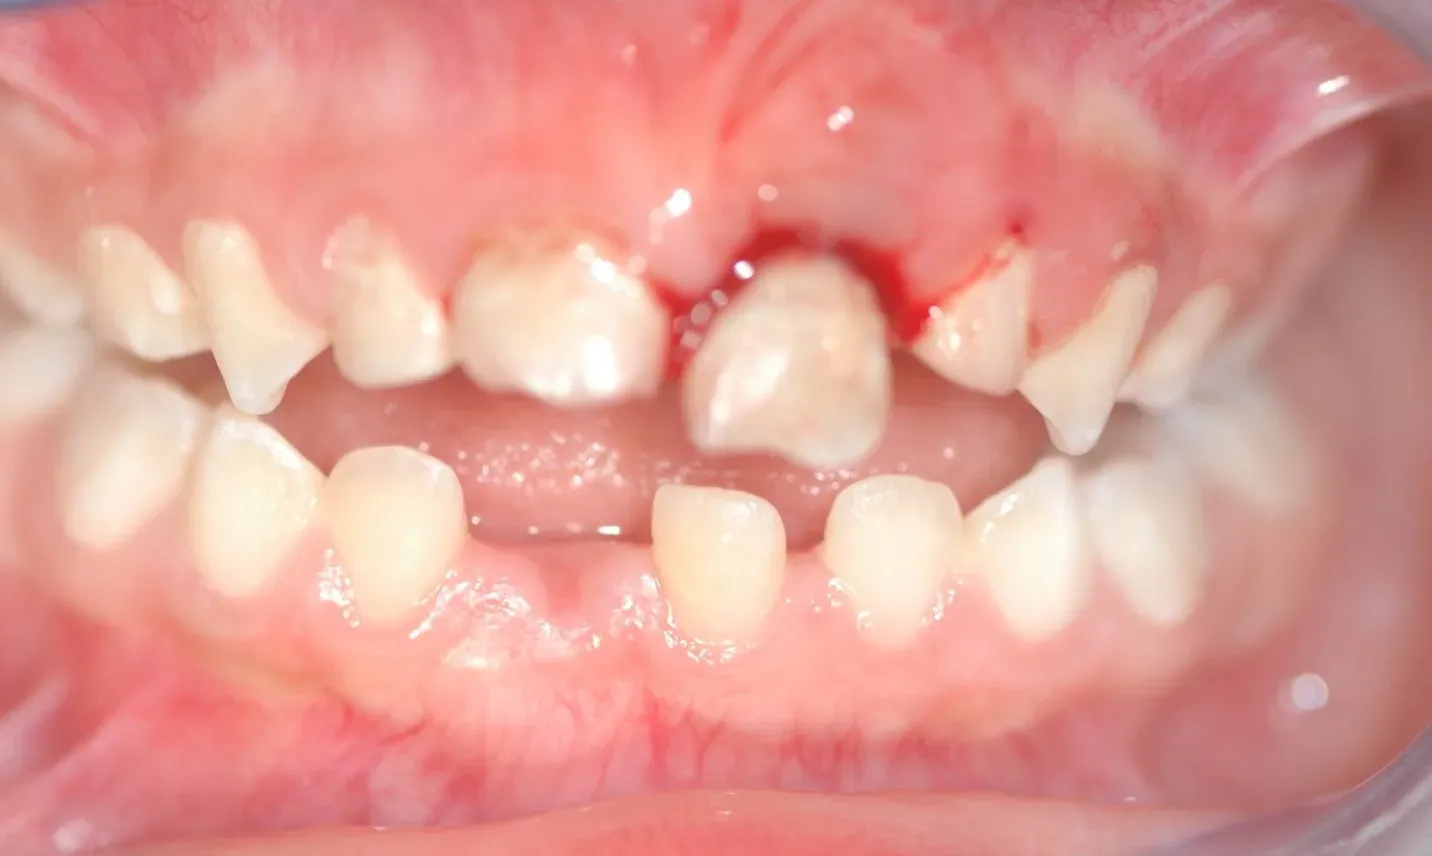

Schwere Zahnverletzung im Milchgebiß.

Bei Verletzungen an Milchzähnen hat der Schutz des nachfolgenden Zahnes Priorität. Sie werden daher anders behandelt als Unfälle an bleibenden Zähnen. Eine sofortige Vorstellung beim Zahnarzt ist auch bei Milchzahnunfällen immer erforderlich.

Milchzahnverletzung im Alter von drei Jahren: Der Zahn wurde durch den Sturz fast vollständig in den Knochen gedrückt. Diese Art der Verletzung führt oft zu schweren Schäden des bleibenden Zahnes.